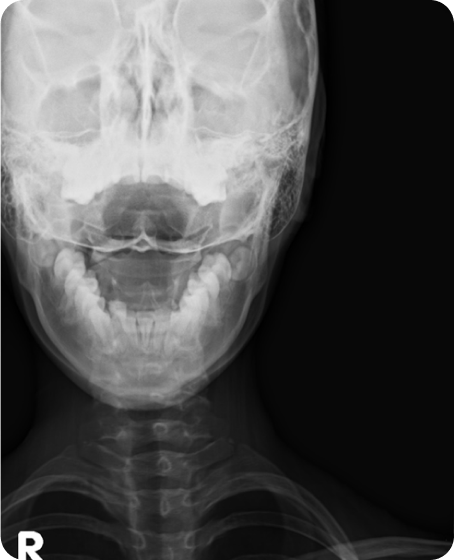

▲ 치료 전 (2016년 1월 21일)